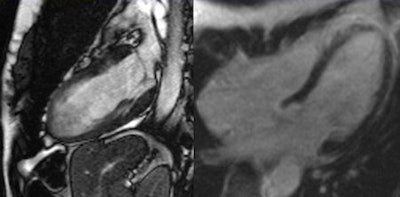

Hypertensive heart disease. General MRI features include concentric hypertrophy of the left ventricular (LV) myocardium, end-diastolic thickness of interventricular septum >13 mm, impaired systolic LV function, scattered zones of late enhancement, and sometimes (as in this case) diffuse edema pattern.As for the prognosis, the primary endpoints are MACE (major adverse cardiac events: death, stroke, heart failure), recurrent hospitalization, and the de novo interventional procedure, he concluded.